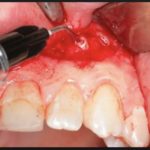

Во время сильного воспаления сначала освобождают каналы от содержимого. Для этого применяют дренаж через десну, корневые каналы или лунку, если зуб был удален. Если апикальный периодонтит локализован глубже, разрезают переходную складку. Обычно этот метод применяется при абсцессе, которое является одним из осложнений заболевания. Все манипуляции осуществляют под местным обезболиванием, чтобы добраться до пораженного участка без причинения дискомфорта пациенту.